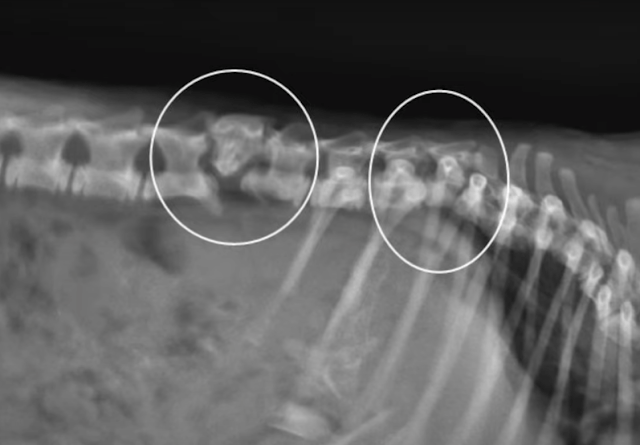

Abe’s x-rays printed that he had damaged his returned in two places. Due to the damage, he would in no way stroll again. Abe’s rescuers knew that this would make it difficult to locate him a alwaysdomestic however they have been no longer going to supply up on the candy dog. It used to betime to make some greater calls and discover a area for Abe to go as soon as he was once medically cleared.